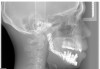

Prior to implant placement, the vertical dimension of occlusion had to be reestablished and a new functional posterior occlusal plane developed. Within this framework, the axial position of the implants could be established. However, the positions of these implants were not solely predetermined by the bony architecture of the newly reconstructed mandible but also could be altered to conform to the proportional harmony of the lower face. To assist in this determination, a left lateral skull film was obtained (Figure 7) and an analysis of facial form, vertical dimension, and incisor position was performed. It was determined that the vertical dimension of the lower face would need to be increased; the posterior occlusal plane would need to be intruded; and the axial position of the lower incisor implants would have to be upright over the newly augmented ridge. In order to establish an esthetic anterior occlusal plane, the upper incisors would have to be retracted without extrusion.9 Final vertical dimension was confirmed by a CBCT scan with a modified surgical guide in place (Figure 8), and this same guide was used for the placement of 10 endosseous dental implants. Then, a transitional lower denture was fabricated and orthodontic treatment was instituted while the implants were allowed to integrate.

Figure 8  CBCT scan with the surgical guide to establish vertical dimension of occlusion below, which can be seen in the TBP and particulate bone fill.

Figure 8